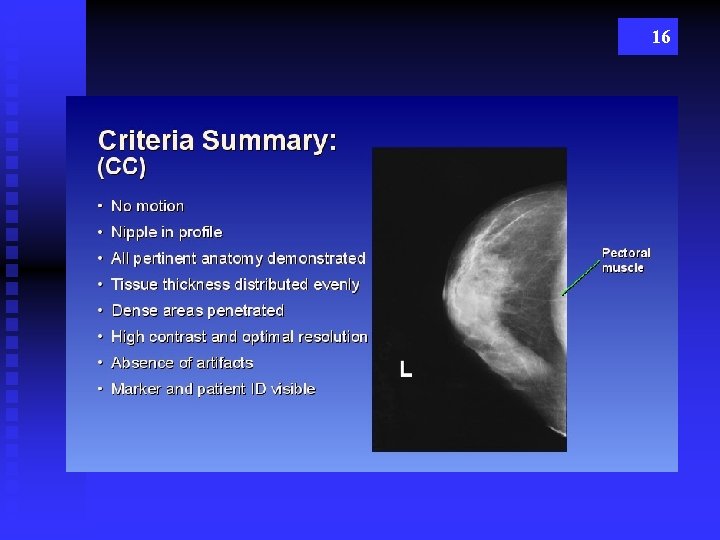

15 CC

16